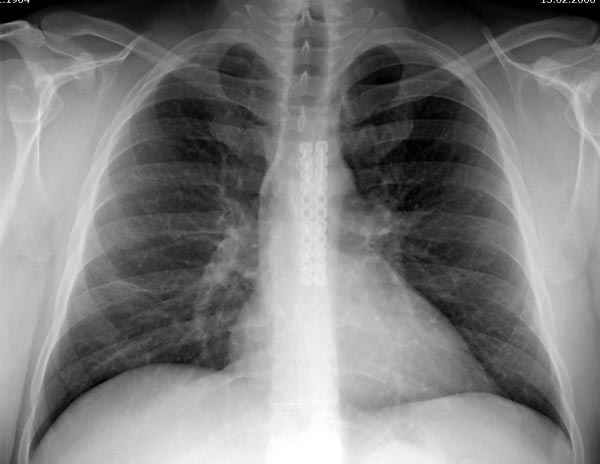

Sorry основной снимок